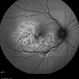

- macula serpiginous choroidopathy

- Tom Steele, CRA

TRC 50ex - Description

- 10/21/2009